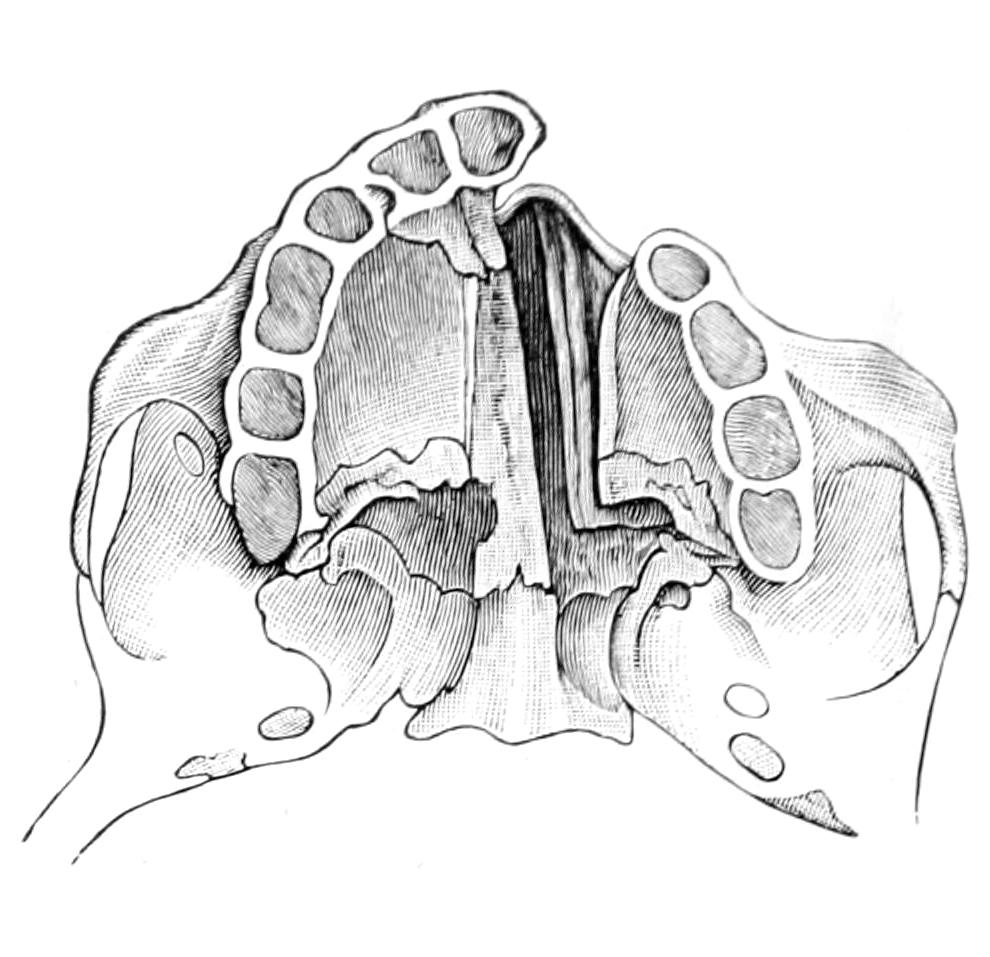

Fig. 1

Congenital hypertrophy: gigantism of both lower extremities. (Case of Dr. Graefe [Sandusky].)